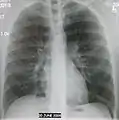

| A chest X-ray showing a very prominent wedge-shape bacterial pneumonia in the right lung | |

Normal AP CXR

Normal lateral CXR

AP CXR showing left lower lobe pneumonia associated with a small left sided pleural effusion

AP CXR showing right lower lobe pneumonia

AP CXR showing pneumonia of the lingula of the left lung

Right upper lobe pneumonia as marked by the circle.

Left upper lobe pneumonia with a small pleural effusion.

Right lower lobe pneumonia as seen on a lateral CXR